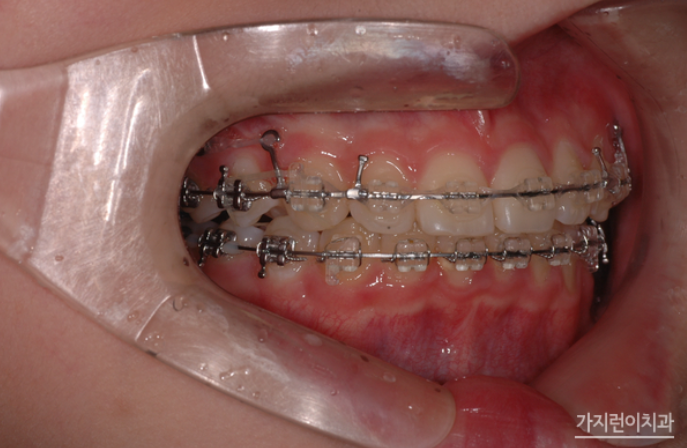

본원에서도 성장기 성장조절치료를 위해 교정용 헤드기어를 사용한 치료를 진행하고 있는데요. 아래턱이 과성장하는 경향이 있는 성장기 어린이는 밴드의 탄력을 활용하여 치열을 전체적으로 당겨 주는 교정용 헤드기어 장치를 착용하여 교정치료를 시행해볼 수 있습니다.

교정용 헤드기어와 스크류를 적극 활용한 케이스라고 할 수 있는데요. 헤드기어의 경우 통상적으로 하루에 12시간 이상 착용을 해야 하기 때문에 주로 취침 시 착용할 것을 권고하는데요. 임의대로 시간을 조절해 착용해서는 안 됩니다. 제대로 시간을 지키지 않을 시 어금니가 이동하지 않아 충분한 공간 확보가 어려워져 결국 발치가 할 수도 있는데요. 때문에 치아의 이동양상에 따라 치과를 방문해 팽팽함을 유지해야 합니다. 여기에 뻐드러진 앞니가 제자리를 찾을 수 있도록 미니스크류를 식립하여 위턱 전체 치열을 후방으로 이동시켰는데요.